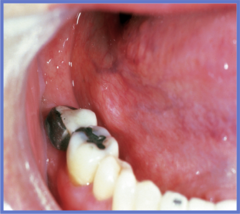

Salivary stone in duct (blockage)

Sialolith